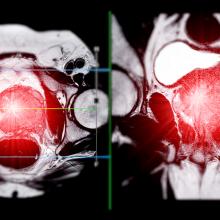

Wyatt and co-authors discovered that blood samples from a patient population gave them insights into which patients had cancer that was already resistant to therapies or who would very rapidly develop treatment-resistance. Within a large-scale randomized clinical trial, the team tested for DNA changes within prostate cancer genes that could drive resistance to treatments in patients with a metastatic form of the disease—when the prostate cancer has spread to other parts of the body.

Using these blood samples, researchers identified two genetic markers—mutations within the DNA repair gene BRCA2 and the common cancer gene TP53—that lead to highly treatment-resistant cancer that can shorten the lifespans of patients.

Up to 30 per cent of metastatic prostate cancer patients do not respond to either of the leading prostate cancer therapies: abiraterone and enzalutamide. Patients with mutations in the BRCA2 gene have prostate cancer that progresses on average six times faster. Those with TP53 mutations see their prostate cancer progress three times faster than patients without these gene mutations.